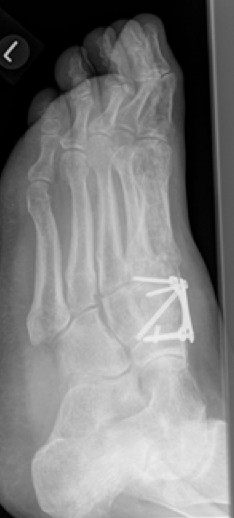

Bei einer Verlaufskontrolle im Juli 2017 ergab sich bei der Röntgenuntersuchung eine Fehllage einer Plattenschraube, die damit das TMT 2 überbrückte.

5.- 07/2017 Schraubenfehllage : Schraube erreicht Basis MT2 und überbrückt TMT 2